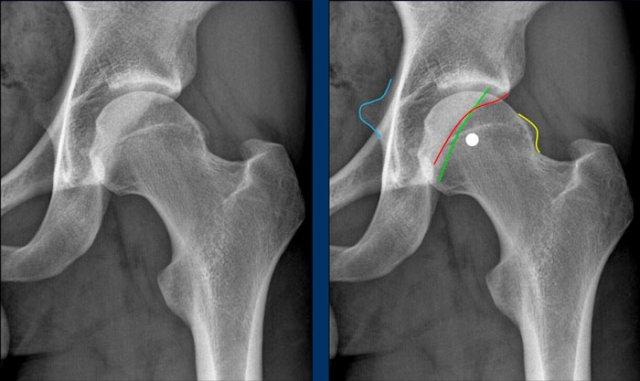

Đây là một ví dụ khác về hình thái dạng kẹp trên hình ảnh được phóng to từ

phim X-quang khung chậu tư thế AP.

Có dấu hiệu giao chéo tinh tế.

Ngoài ra còn có dấu hiệu thành sau và dấu hiệu gai ngồi.

Lưu ý rằng còn có hình thái cam (đường vàng).

Đây là một ví dụ khác về hình thái kiểu kẹp và kiểu cam trên phim X-quang khung chậu tư thế AP.

Cuộn qua các hình ảnh.